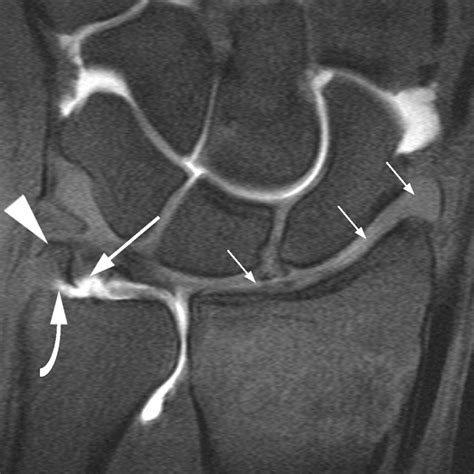

• Imaging Tests: X-rays, MRI, or CT scans may be ordered to visualize the knee joint and confirm the diagnosis. MRI is particularly useful for detecting soft tissue injuries like cartilage tears.